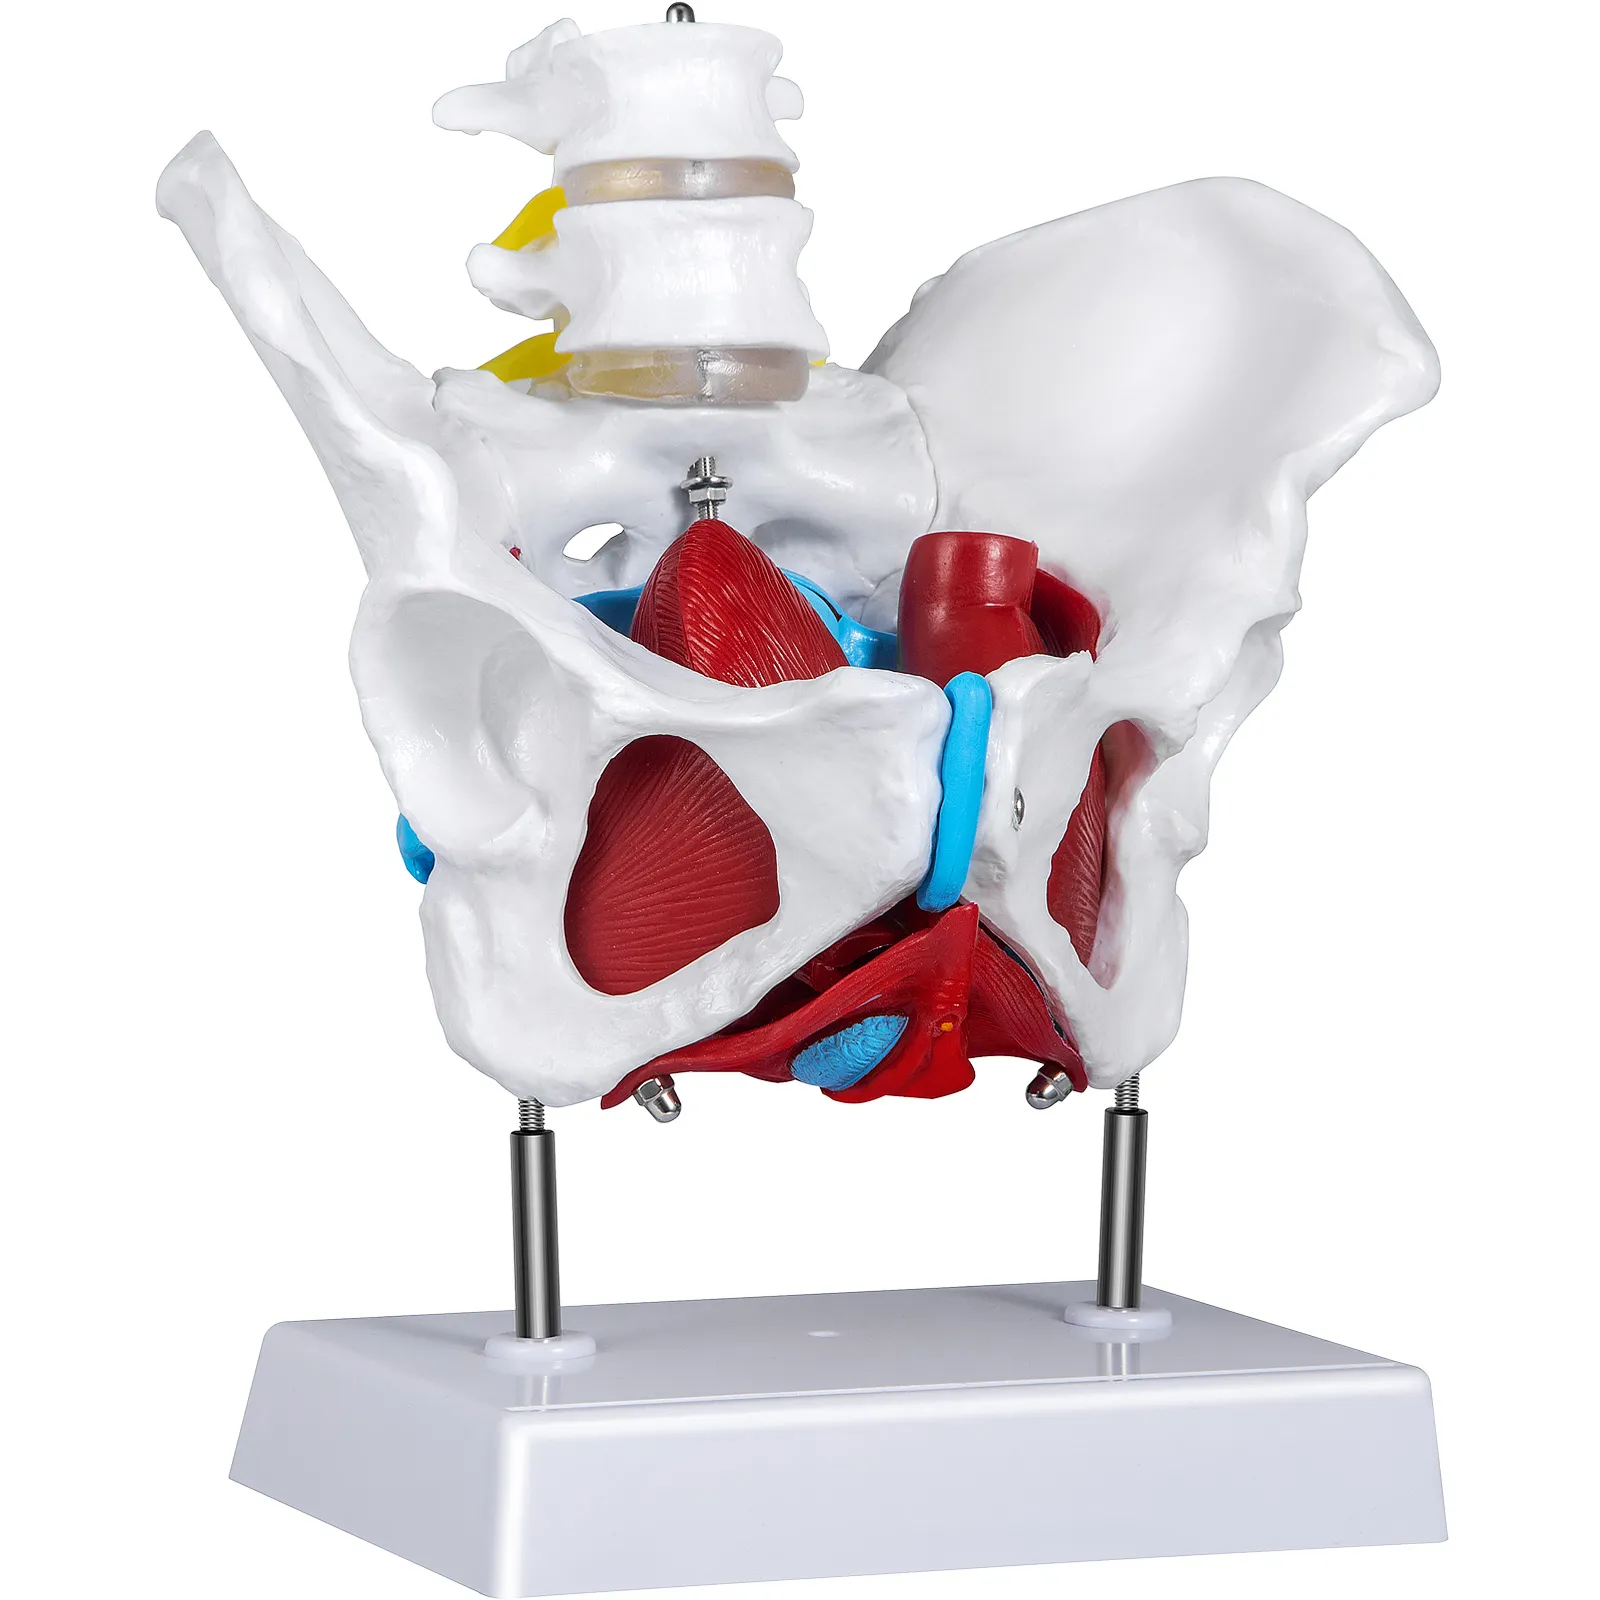

- 【STRUTTURA RIMOVIBILE】 - Il modello del bacino femminile può essere diviso in cinque parti, visualizzando ed etichettando accuratamente ogni area del bacino con colori diversi. Il modello permette di osservare la struttura interna del bacino femminile da tutte le angolazioni per imparare pelvi femminile meglio.

- 【SIMULAZIONE UMANA ACCURATA】 - Il Modello di Pavimento Pelvico è progettato da esperti di ricerca sul bacino per una coerenza accurata al 100% con la struttura di base del bacino femminile, in linea con le dimensioni effettive del bacino femminile. Pertanto, il modello di pavimento pelvico a grandezza naturale è la scelta ideale per la ricerca anatomica del bacino femminile.

Il modello ne contiene 4 parti removibili ed è una replica approssimativamente a grandezza naturale. Come tutte le strutture anatomiche, non esiste una dimensione standard. Il perineo,recta, la vescica e il retto sono facilmente rimovibili. Il modello del bacino sarà un ottimo complemento alle cliniche ginecologiche o agli studenti che ricevono un'educazione sanitaria.

Il Modello di Pavimento Pelvico è apribile ed è facile da montare e smontare. Da tutti gli angoli di osservazione, gli studenti sono in grado di acquisire una migliore comprensione dell'anatomia femminile.

Dettagli con Codice Colore

Il modello di pavimento pelvico con muscoli è dipinto a mano con diversi colori per identificare facilmente le varie parti e strutture del bacino. Puoi apprendere le conoscenze di base delle costruzioni del bacino femminile attraverso il modello senza sforzo.

Modello Anatomico Realistico

Per la professionalità e l'accuratezza del modello, le dimensioni del modello sono le stesse del bacino femminile effettivo e ogni parte è realistica. È appositamente progettato da esperti di ricerca sul bacino femminile per la ricerca, l'apprendimento e l'addestramento dell'anatomia del bacino.